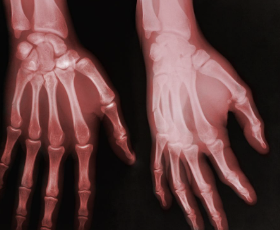

손가락 관절염 초기증상 원인 치료방법 등 정보에 대해 정리해드리도록 하겠습니다. 손가락 관절염은 손가락의 관절에 염증이 생겨 손가락의 움직임이 제한되는 질환입니다. 초기증상으로는 손가락 관절의 미세한 통증과 감각 이상이 나타날 수 있으며, 손가락을 움직일 때 뻣뻣함을 느낄 수 있습니다. 또한, 손가락 끝에 결절이 생길 수 있으며, 이러한 결절은 통증이나 감각 이상을 유발할 수 있습니다.